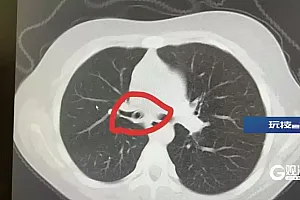

中南大学湘雅二医院眼科主治医生介绍

可以看到晶体里面有明显脱位

玻璃体里有很多积血

需要进行眼球摘除手术